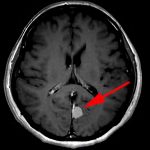

134

'19年10月

70代

左側頭葉膠芽腫

頭蓋内腫瘍摘出術

No.’19_35 手術前1

No.’19_35 手術前2